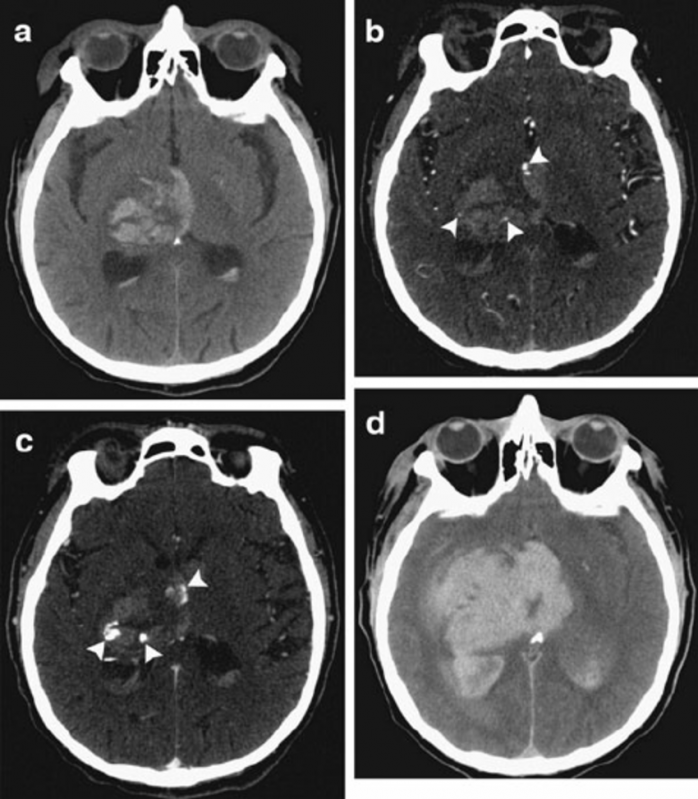

Às tomografias são uma maneira não invasiva e sem causar dor ao paciente, é usado um equipamento de raio x que ao passar ao redor do paciente cria várias imagens do interior do corpo, esse método é feito com rapidez e segurança. As imagens são analisadas e os dados possibilitam que seja feito um diagnóstico sobre o paciente, pois é permitido saber a forma, tamanho, densidade e textura do local dos órgãos do paciente, possibilitando fazer o diagnóstico e acompanhar tumores doenças infecciosas, traumas e distúrbios ósseos.